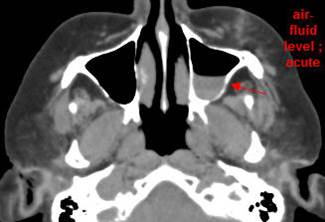

Central Skull Base

There is a fracture of the greater or lesser wing of the sphenoid bone or basisphenoid.

Midface Structures and Mandible

There is bony injury of the body, alveolar ridge, premaxilla, the infraorbital rim, the palatine or the frontal process of the maxillary bones on either side.

The pterygoid processes of the sphenoid bone are fractured.